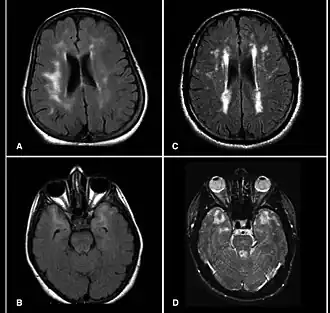

MRI van patiënten met het CADASIL waarin meerdere laesies te zien zijn

Het CADASIL-syndroom (cerebrale autosomale dominant arteriopathie met subcorticale infarcten en leukencefalopathie) is de meest voorkomende vorm van erfelijke beroertes, en wordt verondersteld veroorzaakt te worden door mutaties van het Notch 3-gen op chromosoom 19.[1]

De aandoening is een vorm van leukodystrofie. De meest voorkomende klinische manifestaties zijn migraine, hoofdpijn en TIA's of beroertes die gemiddeld tussen 40- en 50-jarige leeftijd optreden, hoewel het ook is gevonden in individuen van 20 tot 70 jaar. Met DNA-onderzoek kan de aanwezigheid van de NOTCH-3 variant die CADASIL veroorzaakt worden aangetoond. Dit onderzoek kan ook worden uitgevoerd voor de ziekte zich manifesteert.[2]